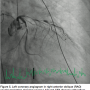

Little did I anticipate that this patient would have the worst peripheral vascular and coronary artery disease I had seen in ten years. The procedure began from the femoral approach since she had bilateral wrist contractures and no pulses. Ultrasound-guided femoral artery access was used since there were no palpable femoral pulses. After an hour of attempts for access, we found that the right iliac artery was 100% occluded and the left femoral and iliac arteries were diffusely diseased, with serial 90% lesions to the aortic junction (Figures 2-3). We were able to pass 5 French catheters to the coronary ostia and found that both the left and right

coronary arteries were severely and diffusely diseased, with multiple and serial critical lesions throughout (Figures 4-6). The left ventricular end diastolic pressure was 35 mm Hg and ventriculography was deferred. Based on the terrible state of all coronary arteries, the severely impaired left ventricle, and her underlying condition, I felt that PCI was futile. We concluded our procedure at 3am and transferred the patient to the recovery room. She felt she did not want to continue using the supplemental oxygen mask that was needed to maintain her oxygen saturations. She requested we remove the mask and two hours later she succumbed.